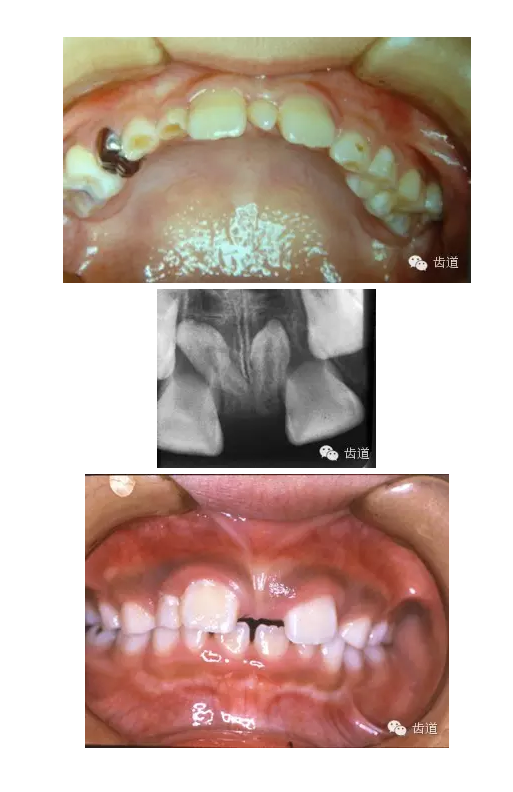

乳牙滯留

乳牙滯留是指繼承恒牙已萌出,未能按時脫落的乳牙,或恒牙未萌出,保留在恒牙列中的乳牙及時拔除

多生牙

超過正常牙數(shù)以外的牙齒

好發(fā)部位:上頜中切牙之間、牙弓末端第三磨牙之后

多呈圓錐形、圓柱形

影響恒牙的發(fā)育和萌出

應及時拔除